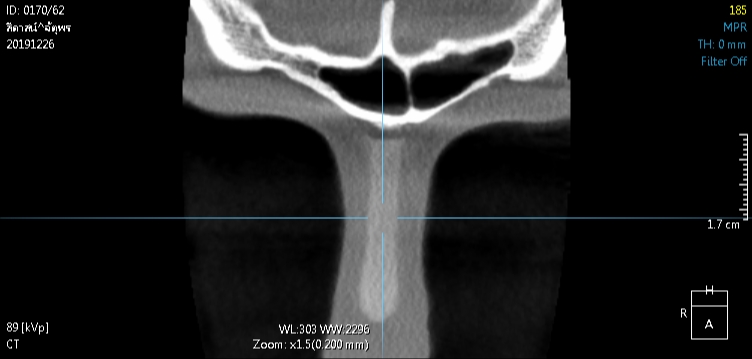

1 ตรวจการเบี้ยวเอียง ปัญหาใหญ่ของการเสริมจมูก ไม่ว่าจะเป็นแบบ openหรือ closed rhinoplasty ก็คือ การเอียง,เบี้ยว คำตอบของผู้ให้กับผู้รับบริการ ที่ไม่ตรงกัน เรามีคำตอบและพิสูจน์ได้ด้วยตาคุณเอง 100% ไม่ว่าจะเป็นที่ไหน โคนหรือปลายจมูก? มากหรือน้อย?

ในกรณีเอียงไม่มาก อาจเป็นสาเหตุให้แกนจมูกใหญ่ หรือ รูจมูกไม่เท่ากันได้ เราสามารถตรวจได้อย่างมั่นใจจากการเห็นภายใน โดยไม่ขึ้นกับอาการบวม เหมือนการตรวจด้วยการมองหรือการคลำ

2 ตรวจดูทรงซิลิโคน จมูกไม่สวยซักที CTบอกได้ เพราะ การตรวจด้วยเครื่องเอกซเรย์คอมพิวเตอร์ความละเอียดสูง สามารถบอกได้ว่าปัญหาความไม่สวยเกิดจากอะไร ทรงSILICONEจมูก ยาวหรือสั้นเกินไป SILICONEตรงหรือโก่ง หัวใหญ่หัวเล็ก การตรวจด้วยเครื่องเอกซเรย์คอมพิวเตอร์ความละเอียดสูง บอกได้ทั้งหมด จะเห็นว่ารูปทรงของSILICONE เมื่อเสริมเข้ามาจริงๆแล้ว ยังต้องมีการปรับตัวให้เข้ากับเนื้อเยื่อรอบด้านทำให้ไม่สามารถประเมินจากภายนอกเพียงอย่างเดียวได้